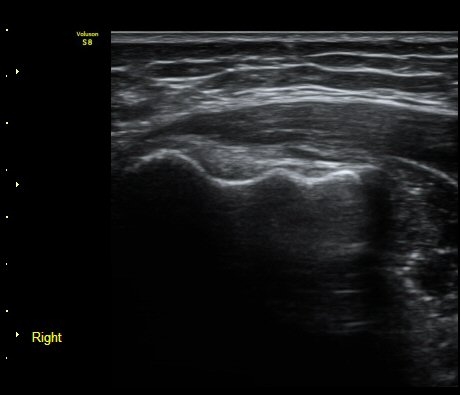

ÃÊÀ½ÆÄ °Ë»ç

³»»ó°ú Á¾´Ü¸é°Ë»ç»ó  ³»ÃøºÎÀδë Àú¿¡ÄÚ ºÎÁ¾°ú ³»»ó°ú ÀÎ´ë ºÎÂøºÎ ÇÇÁú°ñÀÇ ºÒ±ÔÄ¢º¯È­¿Í

°ñÆíÀÌ °üÂûµÇ°í(±×¸² 1, 2, 3, 4) ÀÌ·±¼Ò°ßÀº °ÇÃø°ú ºñ±³ÇÏ¸é ´õ¿í ¶Ñ·ÈÇÔ(±×¸² 5, 6).